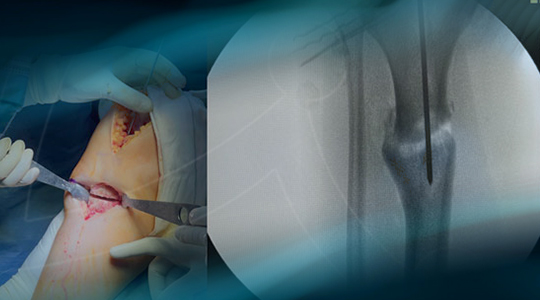

Final strategy decision: Tibial osteotomy by endomedular nailing, Unicompartmental medial knee replacement

Management of a post-traumatic knee pain: Intra-operative images

Intra-operative images